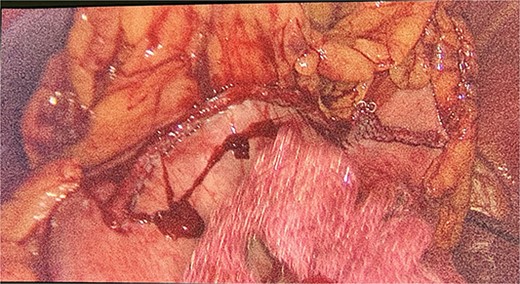

We had to first liberate the adhesions of the colon from a previous operation before gaining entry to the left colon. To do so, we made an incision in the White line of Toldt and dissected the right gastrocolic and splenocholic ligaments. This allowed us to access the retrocolic space and approach the left kidney. We identified the left renal vein and the left suprarenal gland and dissected the gland from the fatty tissue of the kidney. The gastrosplenic ligament was also liberated through the ligation of short gastric arteries. After separating the stomach from the posterior abdominal wall, we located the GIST (Fig. 3) on the posterior part of the fundus and removed it through wedge resection (Fig. 4).